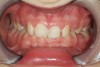

Figure 14  Bruxism triad in a young adult. The pathologic wear, once limited to the anterior teeth, is beginning to appear on the posteriors as guidance is lost. Patient reported sleep issues that became exacerbated with pregnancy. GERD was intermittent until pregnancy then it increased.

Figure 14